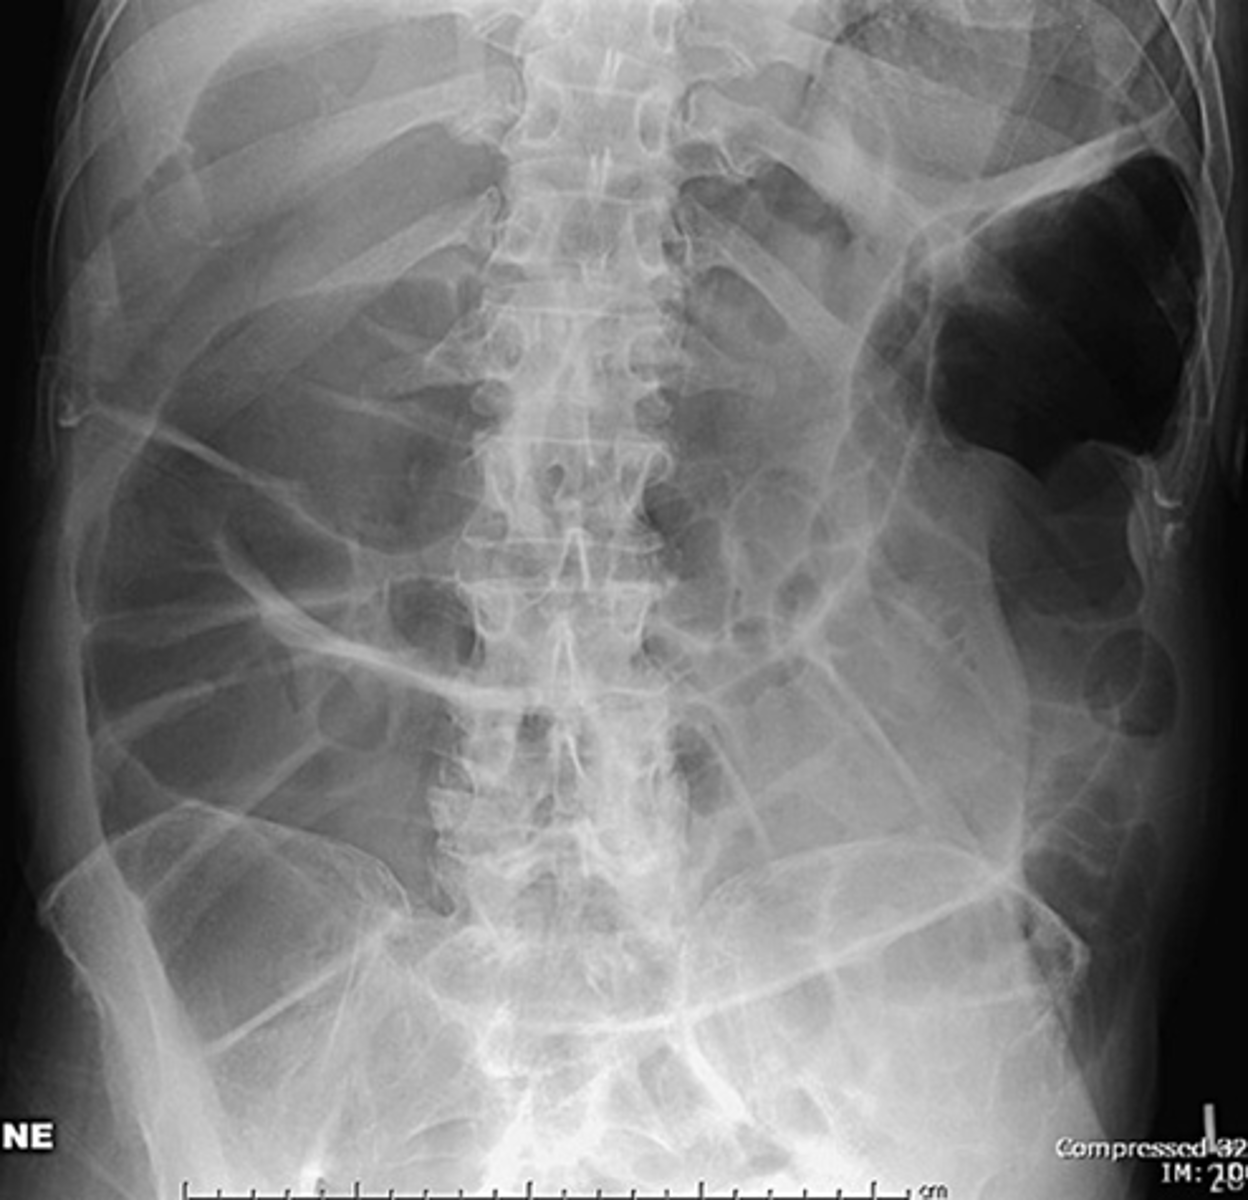

Generalized adynamic ileus, supine (A) and upright abdomen (B).

SOLID WHITE ARROWS: dilated loops of large bowel

DOTTED WHITE ARROWS: dilated loops of small bowel

SOLID BLACK ARROW: Rectum

Gas seen from small bowel to rectum. Patient had no bowel sound and had colon surgery the day before.